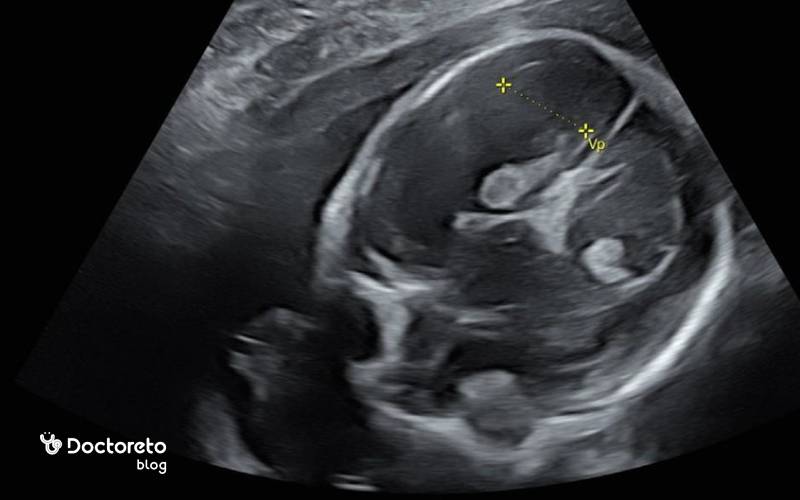

سونوگرافی هفته ۲۷ بارداری

در سونوگرافی هفته بیست و هفتم بارداری تمرکز بر ارزیابی رشد با بیومتری (HC، AC، FL)، برآورد وزن، بررسی مایع آمنیوتیک و محل جفت است. اگر حرکات جنین کم شده باشد یا ریسک بالایی وجود داشته باشد، پروفایل بیوفیزیکال (BPP) یا NST تصویر دقیقتری از وضعیت اکسیژناسیون و تون جنین میدهد. در علائم زایمان زودرس، اندازهگیری طول سرویکس با سونوگرافی ترانسواژینال نسبت به شکمی دقیقتر است.

میانگین وزن نرمال جنین در هفته ۲۷ حدود ۸۵۰ تا ۱۰۰۰ گرم برآورد میشود و قد او از سر تا پاشنه حدود ۳۴ تا ۳۷ سانتیمتر است. این اعداد میانگیناند و قرارگیری در صدکهای مختلف رشدی میتواند طبیعی باشد. پزشک با استفاده از اندازههای دور سر (HC)، دور شکم (AC) و طول استخوان ران (FL) الگوی رشد و وزن جنین ۲۷ هفته را بررسی میکند. اگر وزنگیری کمتر یا بیشتر از انتظار باشد، عوامل مختلفی مانند خطای اندازهگیری، زمانبندی سونوگرافی، وضعیت جفت، مایع آمنیوتیک یا بیماریهای مادری بررسی میشود. در اغلب موارد، پیگیری با یک سونوگرافی رشد بعدی بهترین راه برای قضاوت درست است.

در اواسط بارداری، طول دهانه رحم معمولاً ۳۰ تا ۴۰ میلیمتر است. طول سرویکس کمتر از ۲۵ میلیمتر در حوالی هفتههای ۲۴ تا ۲۸ میتواند با خطر زایمان زودرس همراه باشد و نیاز به پایش نزدیکتر دارد. اگر در بارداری قبلی زایمان زودرس داشتهاید یا علامت نگرانکنندهای دارید، پزشک ممکن است سونوگرافی ترانسواژینال برای اندازهگیری دقیقتر طول سرویکس درخواست کند.